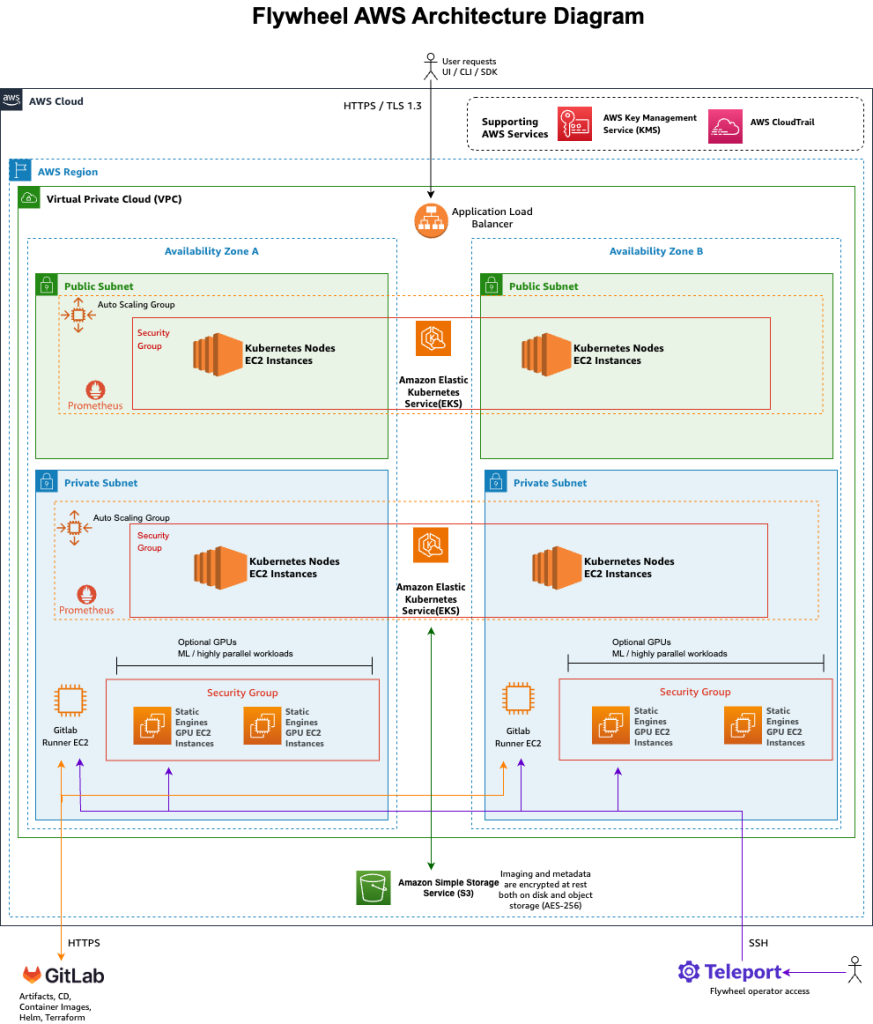

Flywheel runs on AWS to deliver software as a service (SaaS). As shown in Figure 1, Flywheel builds on AWS services, and enables end-to-end processing of medical imaging data at scale. It seamlessly integrates with Amazon Simple Storage Service (Amazon S3) for secure, scalable storage and intelligent cost optimization.

Figure 1 – Flywheel Architecture Diagram